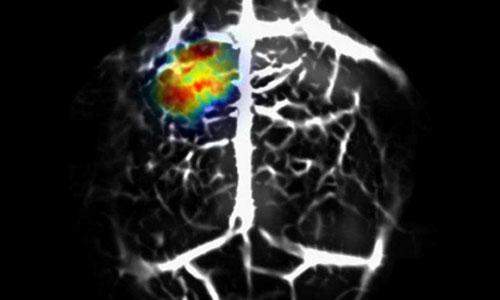

Nat Methods:高端成像技术让癌细胞无所遁形 已有1人参与